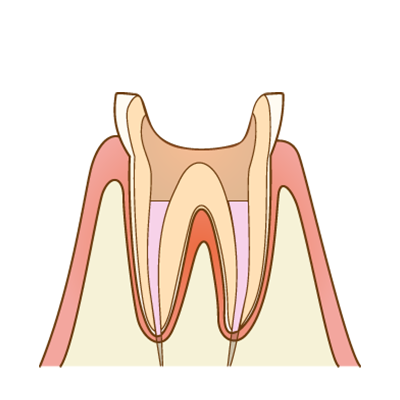

土台(コア)の作製

根管治療後は、被せ物を支えるための土台(コア)を作製します。歯の状態に合わせて、歯に負担の少ない方法を選択します。